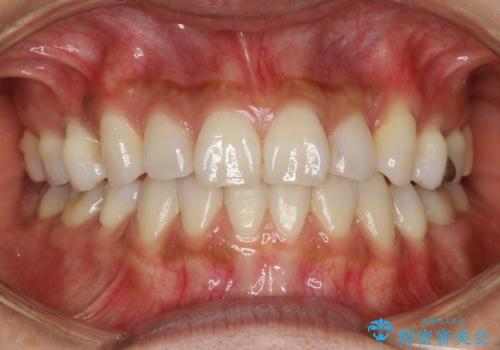

ハーフリンガル抜歯矯正 八重歯を改善する

- 小臼歯4本抜歯によるハーフリンガル・ワイヤー矯正を計画した。

シビアな八重歯がきれいに歯列にはいることにより、笑った時の印象などもかなり大きく変わります。